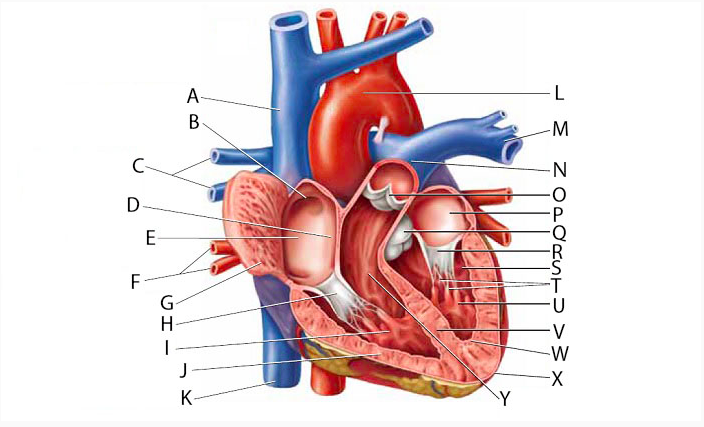

(Common) Hepatic Duct

Anterior interventricular valve

Anterior interventricular sulcus

Posterior interventricular sulcus

Aortic Arch

Aortic Valve (=left semilunar)

Apex (of the heart)

Ascending/descending aorta

Brachiocephalic artery

Brachiocephalic vein

Chordae tendineae

Circumflex branch (of the left coronary artery)

Coronary sinus

Endocardium

Epicardium

interventricular branch of the left coronary artery. = left anterior descending artery (LADA))

Left atrioventricular (=bicuspid, =mitral) valve

Left/right atrium

Left/right auricle

Left/right coronary artery

left/right pulmonary artery/vein

left/right ventricle

Myocardium

Papillary muscles

Pectinate muscles

Pericardial sac (=fibrous pericardium)

N

M

N

Pulmonary trunk

O

Pulmonary valve (=right semilunar)

A & B

D & E

I

H

G

S & T

A & T

Superior/inferior vena cava

U